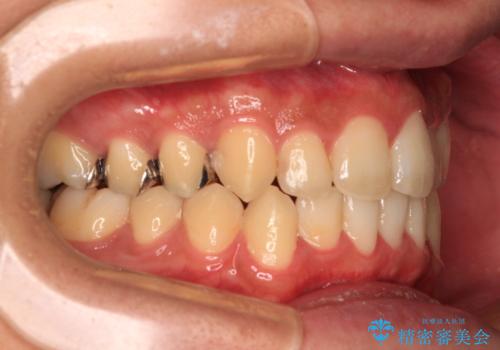

前歯のクロスバイト インビザラインによる矯正治療

- 上下のクロスバイトと前歯のデコボコを気にして来院された患者様です。

インビザラインを用い、IPR(歯と歯の間を削る)と歯列全体を拡大させることで、歯並びを整えていくこととしました。